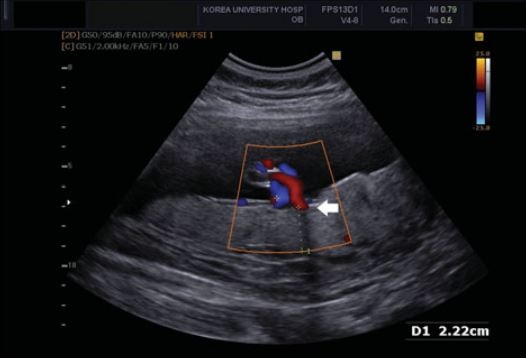

°í·Á´ëÇб³ ¾È¾Ïº´¿ø »êºÎÀΰú ¾È±âÈÆ ±³¼öÆÀ(¾È±âÈÆ·È«¼øÃ¶)ÀÌ ÅÂ¾Æ ¹ßÀ°Áö¿¬°ú °ü·ÃÇØ¼­ Á¶±â ¿¹ÃøÀÌ °¡´ÉÇÑ »õ·Î¿î µµ±¸¸¦ Á¦½ÃÇØ À̸ñÀÌ ÁýÁߵȴÙ.

À̹ø¿¡ ¾È±âÈÆ ±³¼öÆÀÀº ÀÓ½ÅÁ߱⠏ÝÀÇ µÎ²²°¡ žÆÀÇ ¸ö¹«°Ô¿¡ ºñÇØ »ó´ëÀûÀ¸·Î µÎ²¨¿ì¸é ÅÂ¾Æ ¹ßÀ°Áö¿¬ÀÇ À§ÇèÀÌ ³ô´Ù´Â °ÍÀ» ±Ô¸í, ¿©¼ºµé Ãâ»ê¿¡ µµ¿òÀ» ÁÙ ¼ö Àִ »õ·Î¿î ¿¹Ãø¹ýÀ» Á¦½ÃÇß´Ù.

¾È±âÈÆ ±³¼öÆÀÀº À̹ø ¿¬±¸¿¡¼­ 1281¸íÀÇ »ê¸ðÀÇ µ¥ÀÌÅ͸¦ ºñ±³·ºÐ¼®Çߴµ¥ ±× °á°ú, ½Å»ý¾Æ üÁß°ú ÀӽŠÁ߱⠏ݵβ²°¡ ¹ÐÁ¢ÇÑ »ó°ü°ü°è°¡ ÀÖ´Ù´Â °ÍÀ» È®ÀÎÇß´Ù.

¾È ±³¼öÆÀÀº ¿¬±¸¸¦ ÅëÇØ, ÀӽгªÀ̺¸´Ù ÀÛÀº ½Å»ý¾Æ Áß 55.7%ÀÇ ÀÓ½ÅÁ߱⠏ݵβ²(cm)/žƿ¹»ó¸ö¹«°Ô(kg)°¡ 6.3 ÀÌ»óÀÓÀ» ¹ß°ßÇß´Ù.

ƯÈ÷ ÅÂ¹Ý µÎ²²´Â ÃÊÀ½ÆÄ°Ë»ç¸¦ ÅëÇØ °£´ÜÇÏ°Ô ÆÄ¾ÇÇÒ ¼ö ÀÖ¾î ÀÌ °Ë»ç´Â È¿À²¼ºµµ ³ôÀ» °ÍÀ¸·Î ¿¹»óµÈ´Ù.

±×´Â ¶ÇÇÑ "Àڱà ¼öÃà ¹× ÀÌ·Î ÀÎÇØ µÎ²¨¿öÁø Źݿ¡ ÀÇÇØ »ê¼Ò ¹× ¿µ¾çºÐ Àü´ÞÀÌ ¹æÇظ¦ ¹Þ¾Æ ÅÂ¾Æ ¹ßÀ°Áö¿¬ÀÌ ´õ ¸¹ÀÌ ¹ß»ýÇÏ´Â °ÍÀ¸·Î ÃßÁ¤µÇ¸ç Á¤È®ÇÑ ±âÀüÀº Á»´õ ¿¬±¸ÇØ¾ß ÇÒ ºÎºÐ"À̶ó°í ¼³¸íÇß´Ù.

À̹ø ¿¬±¸´Â ³í¹® 'Placental thickness-to-estimated foetal weight ratios and small-for-gestational-age infants at delivery'¸¦ ÅëÇØ ¹ßÇ¥µÆÀ¸¸ç ±¹Á¦»êºÎÀΰúÇÐȸÁö ÃÖ½ÅÈ£¿¡ °ÔÀçµÆ´Ù.